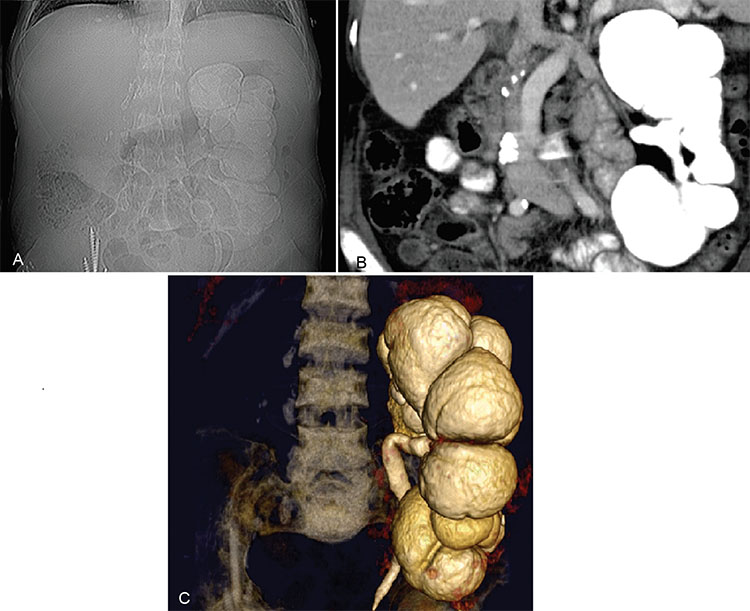

La alteración más precoz se aprecia a nivel de los cálices con erosiones en "apolillado". Ese hallazgo es seguido de una necrosis papilar. Se puede observar una falla renal y una dilatación del sistema pielocaliciliar (Fig. 4). Hallazgos como cavitaciones del parénquima renal o bien cicatrices fibróticas del parénquima se aprecian en estados más avanzados. Calcificaciones con distribución lobar se observan en estadios finales.8 Lesiones similares se pueden encontrar en pielonefritis xantogranulomatosa.

Mujer de 44 años con antecedentes de TBC pulmonar, pleural y genitourinaria, nefrectomizada derecha, enfermedad renal crónica en hemodiálisis, realizó una consulta por dolor abdominal y crisis hipertensiva secundaria. (a y b) Se realizó TC que destacó una marcada dilatación del sistema caliciliar con destrucción caseosa corticalocorticomedular y delparénquimarenal. (c) Se realizóuna reconstrucción de TC en 3D que destacó con mayor énfasis las dilataciones mencionadas. En el examen de orina se aislaron bacilos de Mycobacterium tuberculosis.